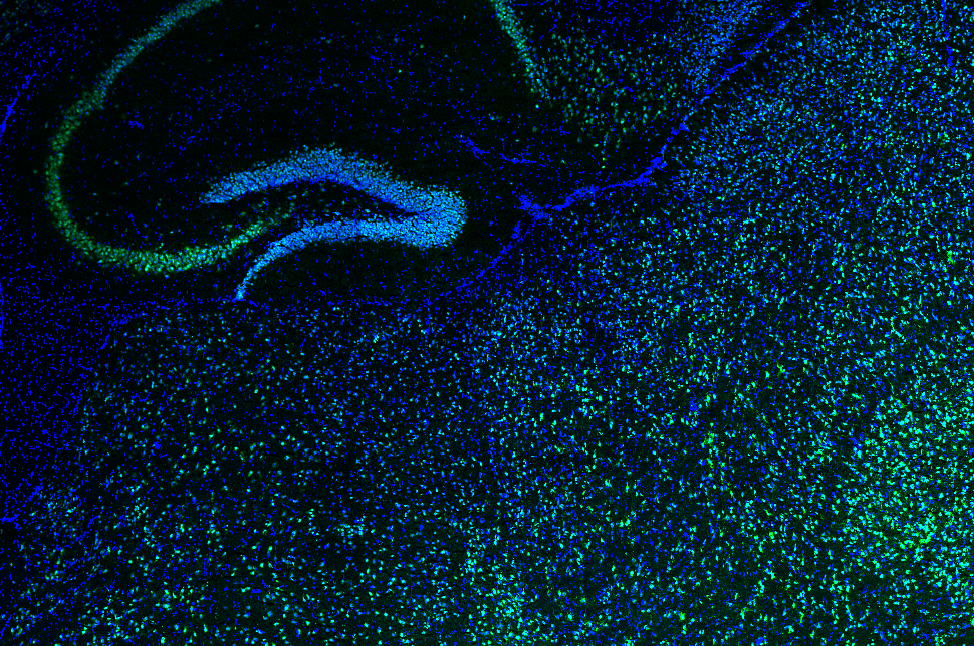

/This award will support the work of graduate student Courtney Whilden on "Investigating Satiety Circuitry Changes in Prader-Willi Syndrome." Experiments are already underway!